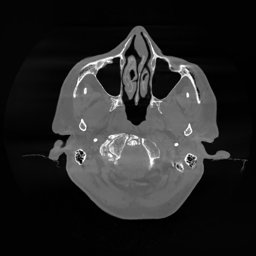

The results for simulated noisy data are shown in Fig. 2. The first and third rows display two representative slices from the test set, and the second and fourth rows present the corresponding error maps. The traditional WCE method suppresses cupping artifacts and recovers some missing anatomical structures but still shows noticeable deviations from the ground truth. Predictions from the four diffusion-based models demonstrate a markedly improved ability to restore anatomical structures. Among them, cDDPM fails to fully reconstruct the patient bed and retains residual noise in its outputs. This noise is attributable to an incomplete reverse denoising process rather than residual Poisson noise, as evidenced in our noise-free experiments (Fig. 5 in the Appendix). PatchDiffusion, diffusionGAN, and I2SB achieve similar visual quality, with I2SB producing the cleanest and most consistent reconstructions.

The experimental results on clinical head data are shown in Fig. 4. The reference images were reconstructed using the fast iterative shrinkage-thresholding algorithm (FISTA) with total variation regularization from non-truncated projection data. In the WCE reconstructions (Fig. 4(b)), severe truncation prevents accurate recovery of anatomical structures outside the FOV. Despite being trained solely on simulated data with a domain gap, all deep learning models can restore a substantial portion of the missing anatomy. Among them, the diffusion-based methods recover soft-tissue boundaries more faithfully than the conventional deep learning approach FBPConvNet, highlighting their stronger image generation capability. However, cDDPM reconstructions exhibit more noticeable noise than those from other methods, consistent with the simulated data results. The patchDiffusion model introduces artifacts within the FOV, likely due to its patch-wise processing strategy. While I2SB shares the same limitations as other diffusion models in perfectly restoring soft-tissue detail, it produces fewer residual noise patterns and fewer artifacts within the FOV boundaries. Overall, Fig. 4 demonstrates the strong efficacy of I2SB in reconstructing real CBCT data.